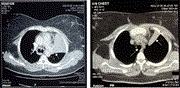

CT-guided radiofrequency neurotomy (RFN) of bilateral T3–4 sympathetic chain combined with bilateral L3 sympathetic ganglion in patient with palmar hyperhidrosis

Shangdao Lai and others

Journal of Surgical Case Reports, Volume 2025, Issue 1, January 2025, rjae808, https://doi.org/10.1093/jscr/rjae808